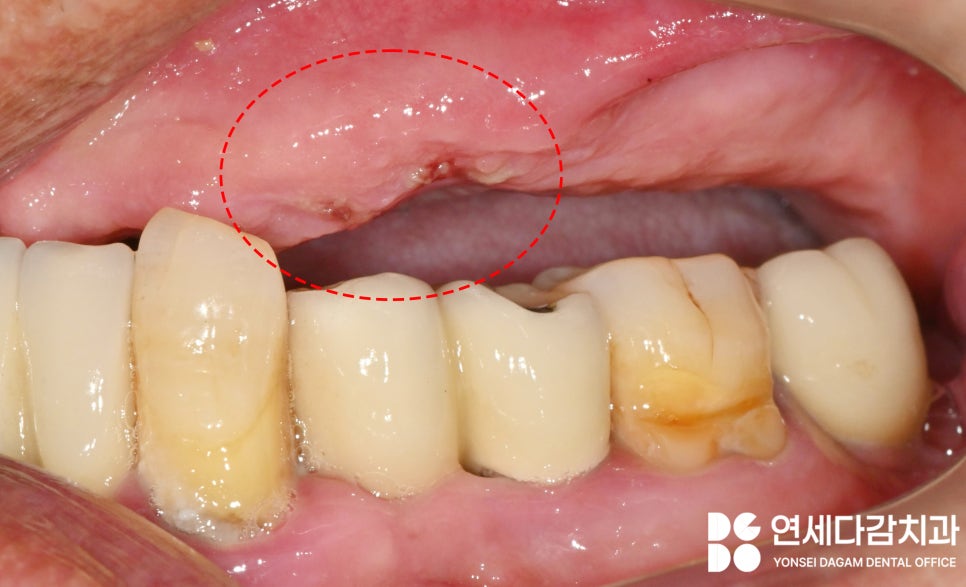

그러나 맞지 않는 틀니를

사용하다 보니,

가락시장역 치과 에서 표시한

부위처럼

잇몸에 상처가 나기도 하죠.